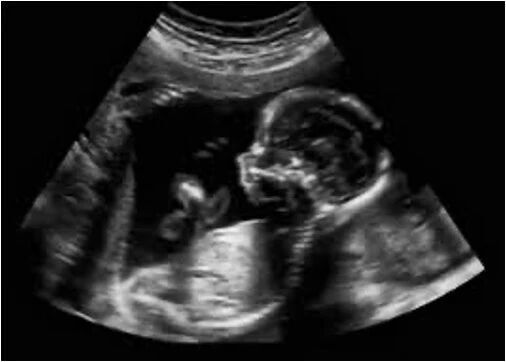

主持人:我想请问刘老师第一个问题是:为什么超声检查在孕妇的产检中如此不可或缺?

刘恒:我身边这一台就是目前医院常规使用的超声诊断设备,包含了设备主机和探头。简单来说,超声就是「用声音看世界」。探头会发出人耳听不见的高频声波,经过处理后形成最终的超声图像。

相较于X光、CT这种放射性检查,超声具有无辐射、可重复性强、实时成像的特点,所以非常适合孕期产检。

在国内,通常孕妇在产前至少要经历五次超声检查,以保证孕妇和胎儿的安全。

主持人:也就意味着,我们每个人在出生前都接触了超声检查?

刘恒:没错。但这个前提是,母亲有条件享受超声检查。今天我们在上海,大家的孕检都很方便,费用也被医保覆盖了,所有孕妇都能享受全孕周的产检服务。

但身处欠发达地区的孕妇是很难享受到超声服务的。首先,不是每家医院都有超声设备。即便有了设备,谁来操作?

在国内,一个超声科医生需要经过长时间的专业学习,加上医院的规范性培训,最后才能上岗。但在非洲,比如马拉维,全国人口超过2100万人,只有四名超声医生。横向类比的话,相当于全上海只有不到10名超声医生,那咱们产检要排到猴年马月。

而在偏远地区,设备、医生、基础设施这三样往往同时缺失。这张图就是非洲的医护人员仍然在用简易的听筒来确认胎心,可见相关设备的缺失是多么严重。

这种缺失代价巨大,全球70%的孕产妇死亡发生在非洲。

主持人:如果要给欠发达地区提供他们用得上的超声设备,我们应该做什么改进?

刘恒:首先是便携,不可能背着一个大机器上山下乡。我们的设备只有一个探头,搭配智能手机或平板进行使用,相当灵活。

其次,操作必须得简单。传统的超声检查非常依赖医生的经验手法,而我们的产品基于6步「盲扫」操作,AI算法自动识别、搜集数据进行分析输出结果。这样即便没有专业的超声医生,经过简单的培训,相关人员都可以快速上手操作。

咱们看到最后的结果:23周零6天。跟23周的体模在一个正常的误差范围之内,还算是比较好的一个结果。

实际在应用中,我们输出的页面上包含六个核心指标:孕龄、胎重、胎位、羊水深度、是否多胎,以及推测的预产期。

主持人:为什么是这六个指标?

刘恒:在很多非洲地区,孕妇记不清末次月经,甚至没有预产期的概念,到了迫不得已才匆忙赶往医院;而孕龄和胎重,就是评估胎儿生长发育的重要参数。

再比方说胎位,如果是非头位,要做剖腹产干预,如果是多胞胎,就要作为高危产妇进行风险预警;包括羊水过少或者过多,都会影响到胎儿的发育。

我们的产品不是为了代替传统超声,而是去解决在没有传统超声的情况下,怎么排查风险的问题。把风险预警提前,主动让产品来适应和满足她们的需求,而不是反过来让人适应工具。